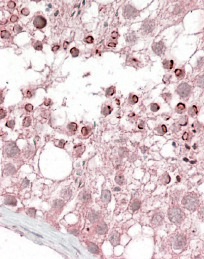

- Main image

- Experimental details

- GTX88638 (3.8?g/ml) staining of paraffin embedded Human Testis. Steamed antigen retrieval with citrate buffer pH 6, AP-staining.